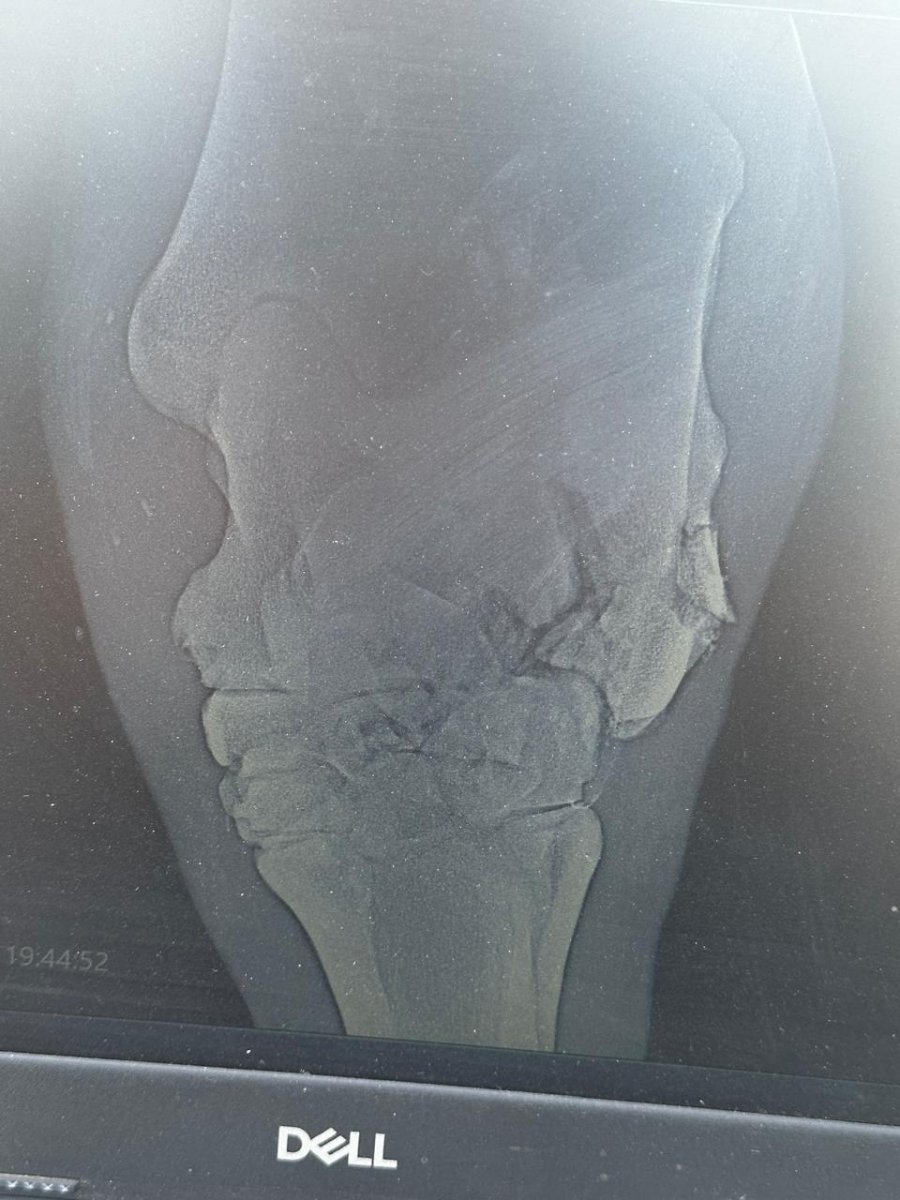

Перелом скакательного сустава

Всем добрый вечер,кто нибудь сталкивался с такой бедой как перелом скакательного сустава,есть шанс вылечить лошадь?

В скакательном суставе много костей. Какая сломана? Есть рентгены?

Что то на рентген как то плохо все это выглядит. И даже если представить себе что все срастётся, то обломки там есть, которые явно надо удалять. Но это не гарантирует излечение. Попробуйте обратиться с рентгеном в новый век или максиму, обязательно проконсультируйтесь. Взвесьте все за и против. Хирургическое вмешательство может как и ускорить процесс, так и явиться последней ветеринарной манипуляций в жизни лошади. Из наркоза лошади выходят не всегда. И даже если все пройдёт хорошо, восстановительный период долгий и сложный.

Перелом оскольчатый,сам по себе скорее всего не зарастёт.Осколки будут смещаться и вызывать постоянное воспаление и конечно боль...Загипсовать не получится,но возможно наложение тугой повязки(флисовые бинты в вашем случае вообще не о чём!).В любом случае нужны противовоспалительные препараты,препараты кальция(возможно тилдрен или осфос), успокоительные на весь период срастания перелома,диета,покой,минимальная нагрузка на ногу(не крутить,не вертеть).Опять же возраст лошади играет большую роль... Конечно нужно консультироваться с хирургами/ортопедами в крупных клиниках.Но на мой взгляд нужно оперировать и удалять осколки.Это риск!Но без операции лошадь может сама доломать себе сустав любым неаккуратным движением...